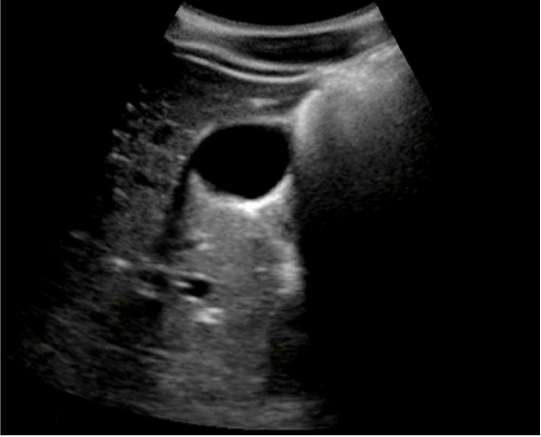

Gallbladder Edge Artifact Image